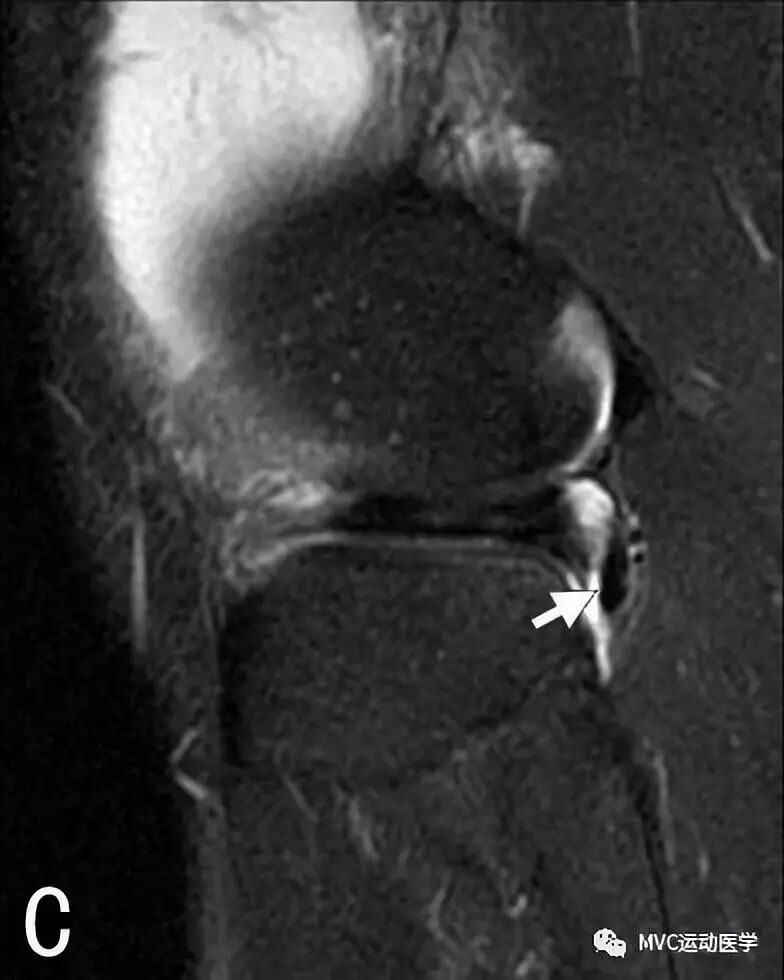

C:矢状位MRI显示腘肌腱(白色箭头),

D:矢状位MRI显示腘肌腱(白色箭头)